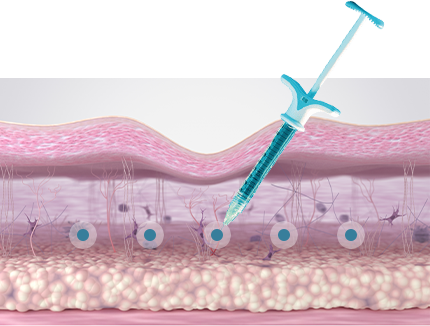

섬유아세포가 대사활동을 하는 동안 섬유아세포에 자극을 주어

콜라겐을 생성하거나, 콜라겐이 서로 합성되는 현상이 일어납니다.